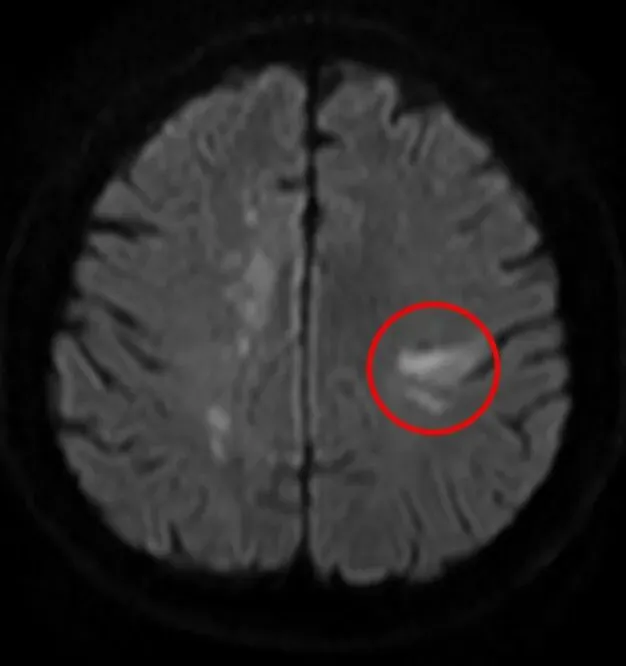

据了解,58岁的男性患者因“双膝关节麻木”入院,初诊时疑似腰椎相关问题。然而次日,患者出现感觉异常症状,经磁共振(MRI)检查确诊为双侧额顶叶多发新鲜脑梗死。医疗团队随即启动抗血小板、强化降脂等常规治疗,患者症状初步好转,但仅3天后病情便再次发作,复查MRI显示新增多处新发脑梗死,症状较前更为明显,常规治疗方案陷入瓶颈。

患者第一次就诊,双侧大脑半球多发脑梗死